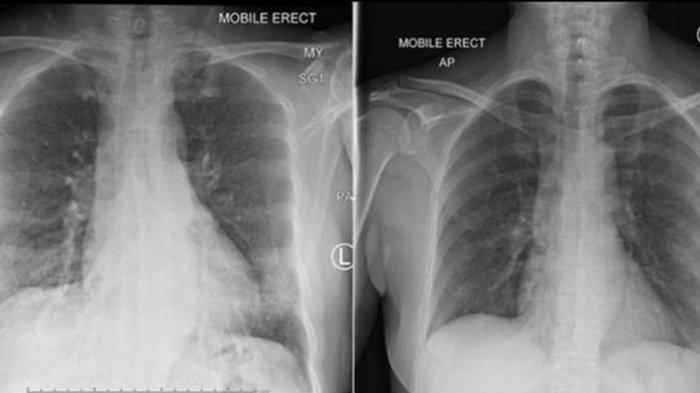

Alasannya ada dua, yakni polusi udara dapat menyebabkan atau memperburuk penyakit pernapasan seperti asma atau penyakit paru obstruktif kronis.

Penyakit-penyakit ini akan membuat tubuh lebih rentan pada efek terburuk infeksi yang menyerang saluran pernapasan atau paru-paru.